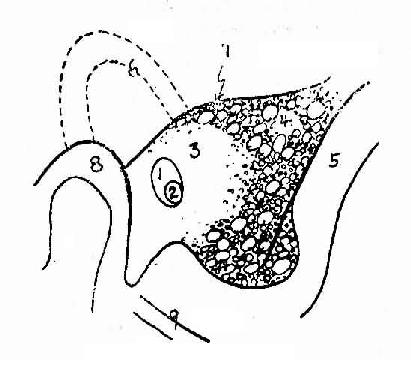

正常影像(图2-19)

1.岩骨呈三角形密影,中间稍偏前可见内、外耳道重迭所致的双环影。

2.颞颌关节位于外耳道之前。

3.鼓窦位于外耳道后上方约1cm。

4.岩骨后缘有乙状窦压迹形成从后向前下行的带状淡影。

5.岩骨上缘密影包括鼓室(即中耳)盖。

6.乳突气房发达者为气化型,气化差如颅骨板障者为板障型,介于两者之间者为混合型。

图2-19 乳突,劳氏位

1.外耳道 2.内耳道 3.鼓 窦 4.乳突气房 5.乙状窦压迹

6.耳 廓 7.鼓室盖 8.颞颌关节 9.后颅凹底